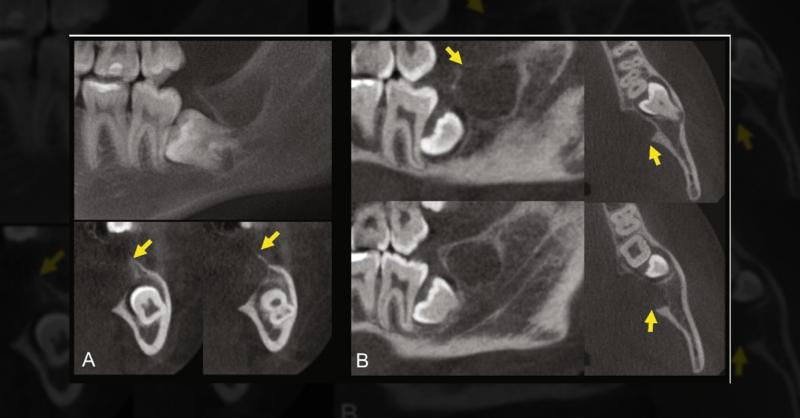

A 17-year-old female sought dental care for a slight swelling in the posterior mandible on the left side. Cone beam computed tomography revealed an osteolytic lesion near the pericoronal follicle of tooth #38, displaying lingual cortical bone expansion and destruction. The patient reported no pain and uncertainty about the lesion's onset during the